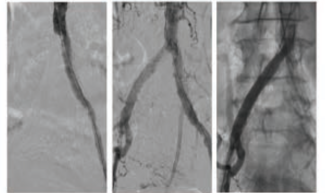

In the case herein, procedural success — defined by stenosis reduction and distal reperfusion of bilateral stumps — was dependent upon gaining arterial access through exotic techniques and crossing the CTOs.